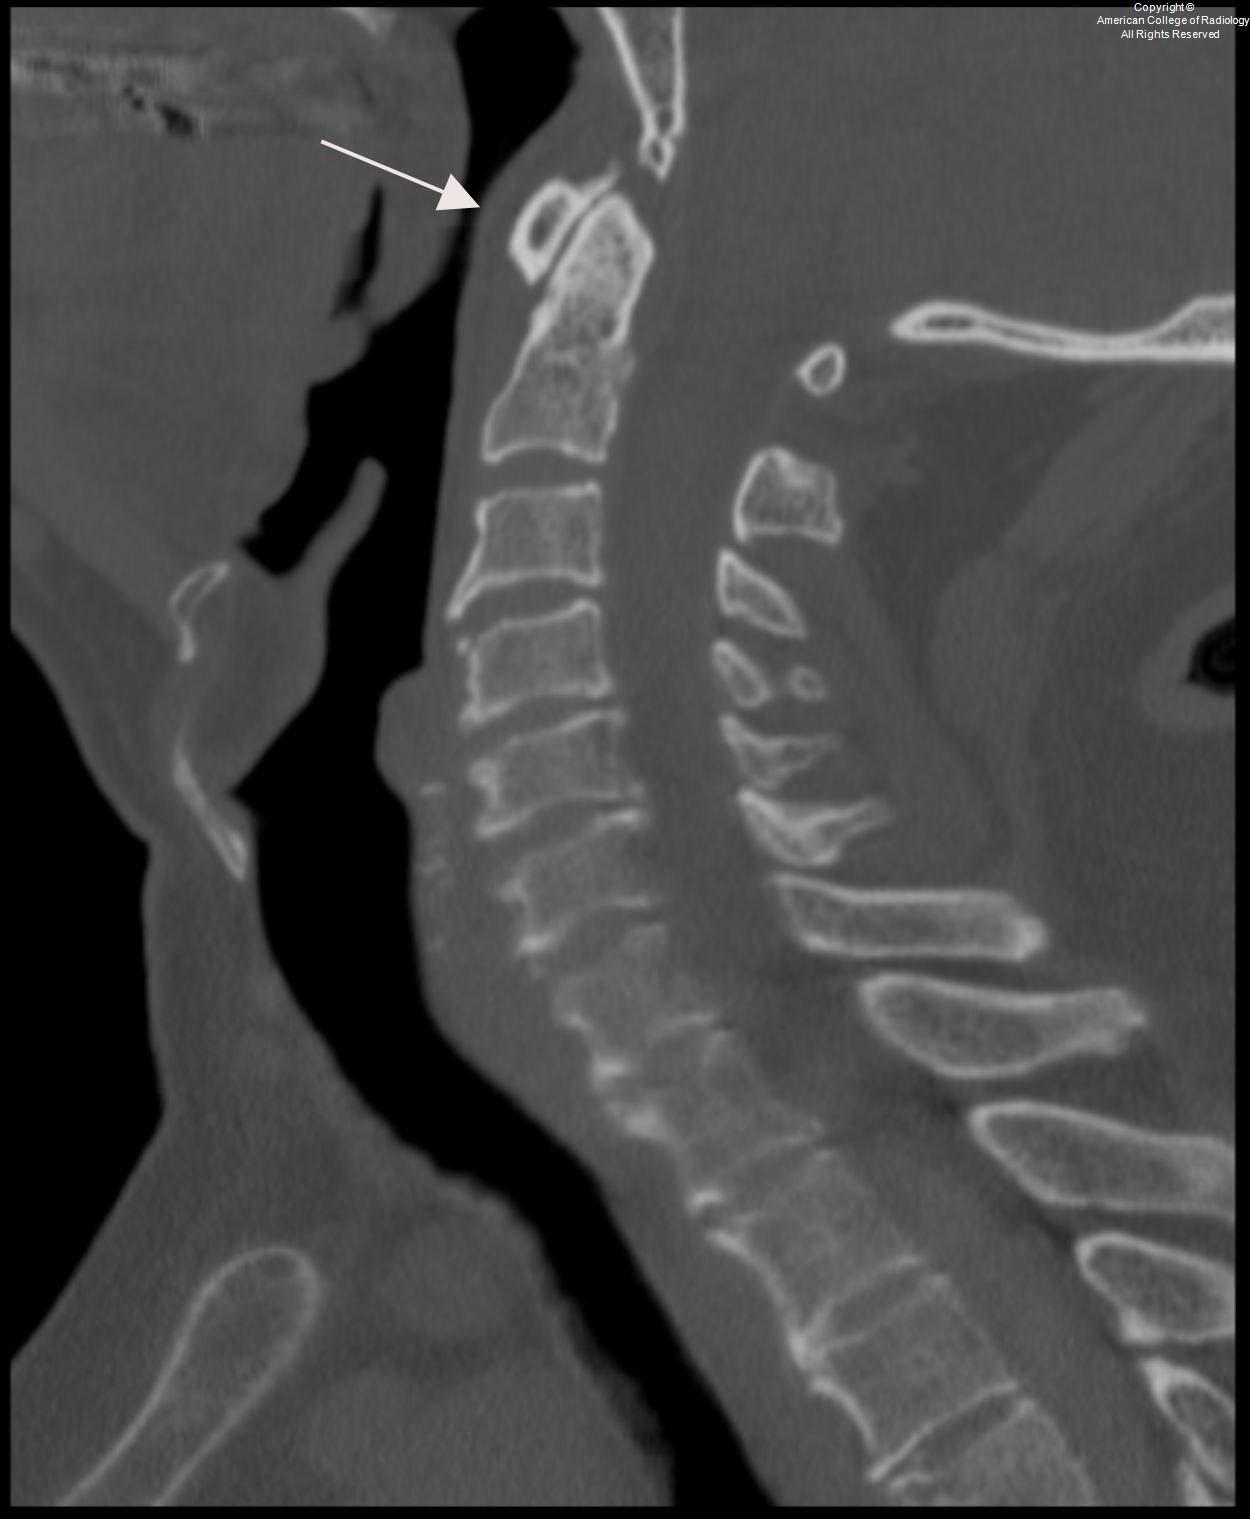

Cspine CT

Look for prevertebral soft tissue swelling SUPERIORLY!!!